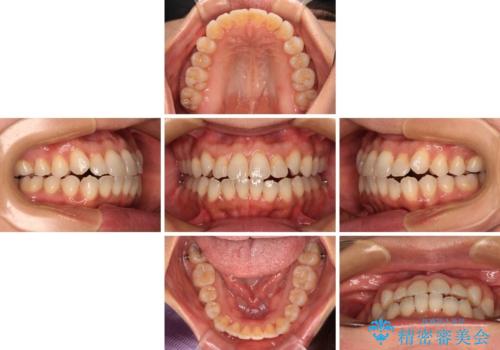

前歯のクロスバイト インビザラインによる矯正治療

インビザラインを用い、IPR(歯と歯の間を削る)と歯列全体を拡大させることで、歯並びを整えていくこととしました。

インビザライン特有の、治療後半に奥歯が咬み合わないという事象が長引きました。

咬み合わないときの対処方法は色々とありますが、ゴムかけなどを活用して噛めるようにしました。